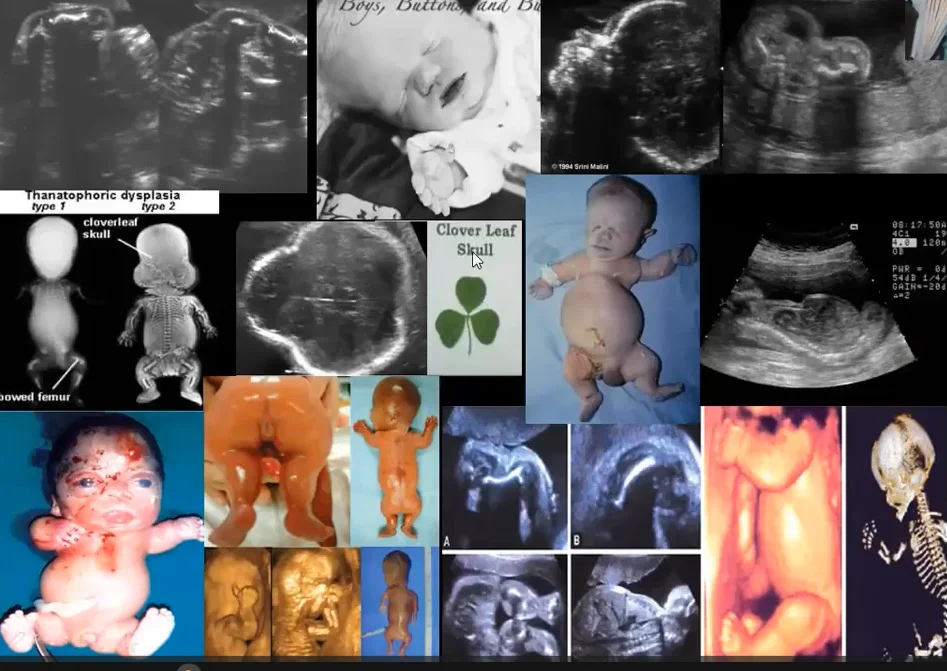

• Tổng quan cơ xương khớp thai nhi (Approach to fetal skeletal)

• Loạn sản xương gây chết thai nhi (Thanatophoric Dysplasia - TD)